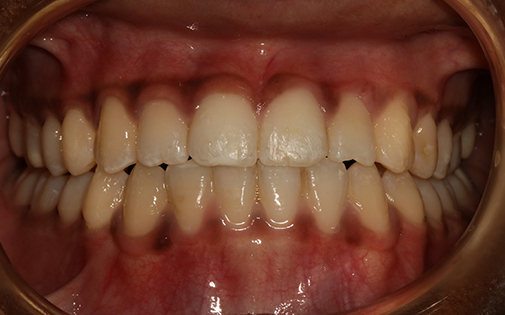

This young patient came to see us aged 11. She had already had trauma to her two upper front teeth. After just 8 months of treatment with Invisalign First the prominence of her upper teeth was reduced from 11mm to 3mm.

Ideally if she had started treatment when she was younger, the trauma could have been prevented but she is now smiling with confidence.